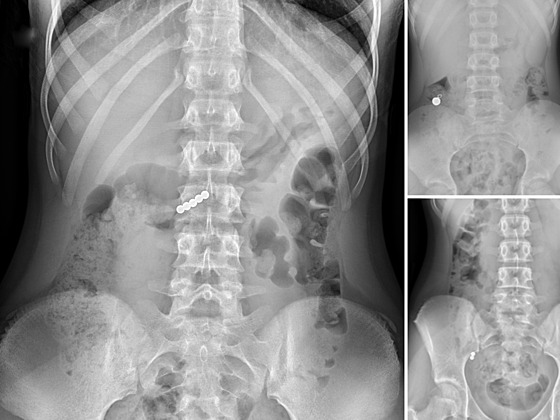

„Při spolknutí více magnetů nebo magnetu a kovového předmětu hrozí jejich spojení, které může k sobě přitáhnout například žaludek a střevo a způsobit jeho poškození, nebo i dokonce proděravění,“ uvedli zástupci nemocnice.

„Pak omylem došlo k polknutí těchto kuliček. Jedna pacientka měla velké štěstí a kuličky vyšly bez problémů, další pacienti ale v současné době zůstávají hospitalizováni,“ uvedla nemocnice.